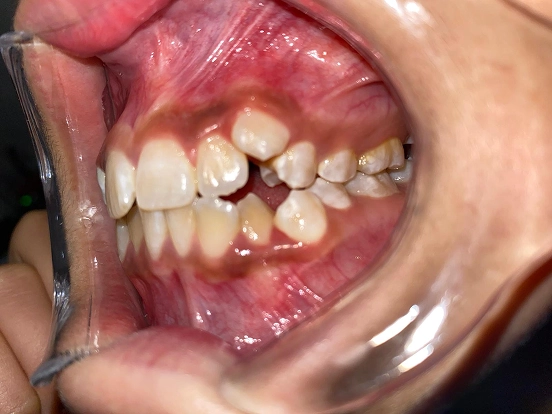

Invisalign DT

DT’s transformation with Invisalign is a perfect example of how advanced orthodontic technology can deliver incredible results. The clear aligners gradually corrected the alignment and bite issues, creating a straighter, healthier, and more attractive smile—all without noticeable brackets or wires.